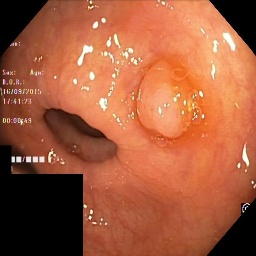

The performance metrics for Edgeconnect and AOTGAN on the validation data after fine-tuning the models, are shown in Table II. In addition to qualitative evaluation, Figure 3 provides example data from the different steps of the PolypConnect pipeline using the EdgeConnect model and the AOTGAN model. Due to obvious visual differences in the generated polyps between the models, we selected the EdgeConnect model as the main polyp inpainting model of the PolypConnect pipeline for further evaluation and qualitative assessment by domain experts.

(a) Refer to caption Refer to caption Refer to caption Refer to caption Refer to caption Refer to caption

(b) Refer to caption Refer to caption Refer to caption Refer to caption Refer to caption Refer to caption

(c) Refer to caption Refer to caption Refer to caption Refer to caption Refer to caption Refer to caption

(d) Refer to caption Refer to caption Refer to caption Refer to caption Refer to caption Refer to caption

(e) Refer to caption Refer to caption Refer to caption Refer to caption Refer to caption Refer to caption

(f) Refer to caption Refer to caption Refer to caption Refer to caption Refer to caption Refer to caption

(g) Refer to caption Refer to caption Refer to caption Refer to caption Refer to caption Refer to caption

(h) Refer to caption Refer to caption Refer to caption Refer to caption Refer to caption Refer to caption

Figure 3: Sample data used and generated in the different steps of PolypConnect pipeline. (a) - real polyp images, (b) - manually annotated polyp masks, (c) - randomly selected colon images used as input to the final step of PolypConnect, (d) - extracted edge images of row c. (e) - extracted edge images of polyp regions of row a using the masks of row b. (f) - combined edge images of row d and f. (g) - generated polyp on the images of row c using EdgeConnect. (h) - generated samples from AOTGAN.